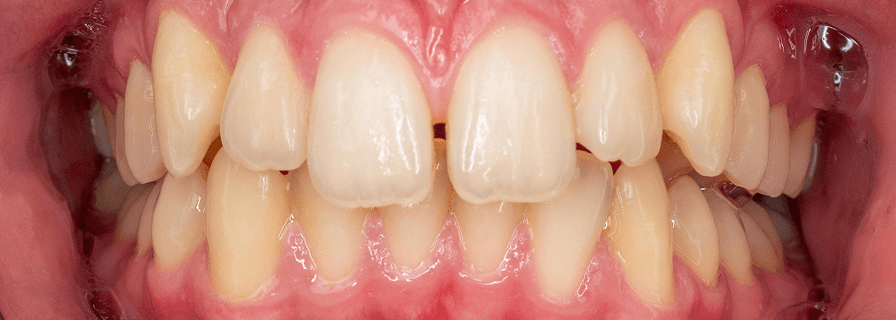

Corectarea Supraacoperirilor și Înghesuirilor Dentare

Pentru acest pacient de 20 de ani am rezolvat problemele complexe de înghesuire și supraacoperire folosind aparat fix bimaxilar. Evaluăm fiecare caz individual pentru a alege cea mai eficientă metodă de tratament. Rezultatele au fost obținute în aproximativ 1 an.